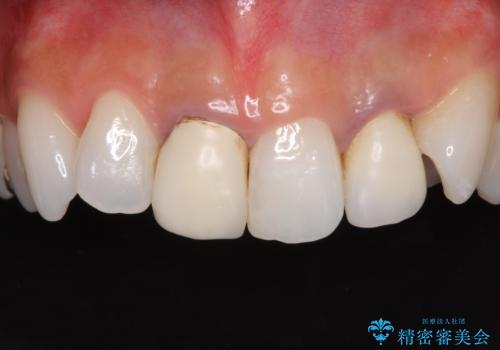

- 20年ほど前に被せた前歯のメタルボンドクラウンの色合いを気にして来院された患者様です。

裏打ちが金属の場合、どうしても金属色を遮蔽しないとならないため、透明感のない色合いとなってしまいます。